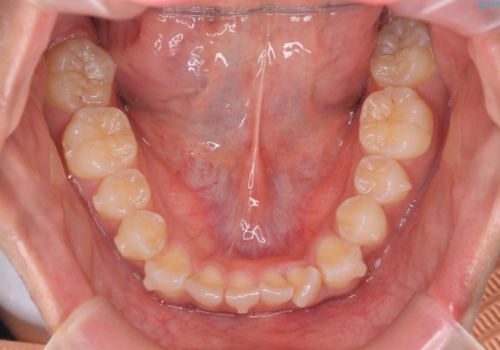

前歯のがたつき 1年かからず治療 マウスピース矯正

- 前歯のがたつきを主訴に来院。

インビザラインで歯を抜かずに並べました。

マウスピースの延長(リファインメント)もなく、短期間で綺麗に並びました。